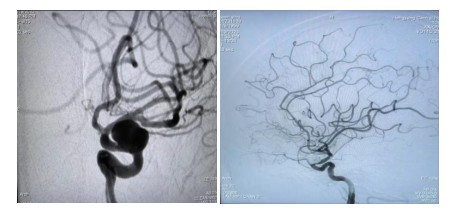

原來(lái)64歲的羅奶奶因?yàn)榘l(fā)現(xiàn)頸動(dòng)脈瘤10余天,來(lái)到衡陽(yáng)市中心醫(yī)院全科醫(yī)學(xué)科住院,在完善腦血管造影檢查后,診斷其為左側(cè)頸內(nèi)動(dòng)脈眼動(dòng)脈段動(dòng)脈瘤,瘤體大,并有分葉子瘤,為高危破裂動(dòng)脈瘤。危急之下,轉(zhuǎn)入神經(jīng)內(nèi)科一病區(qū)準(zhǔn)備進(jìn)行介入手術(shù)治療。

經(jīng)過(guò)充分的術(shù)前準(zhǔn)備工作,神經(jīng)內(nèi)科中心主任丁菁帶領(lǐng)介入團(tuán)隊(duì)與導(dǎo)管室、麻醉科等多學(xué)科共同協(xié)作,順利為羅奶奶實(shí)施了血流導(dǎo)向密網(wǎng)支架輔助下顱內(nèi)動(dòng)脈瘤栓塞術(shù)。手術(shù)過(guò)程順利,術(shù)后羅奶奶在麻醉蘇醒后安返病房。在神經(jīng)內(nèi)科一病區(qū)醫(yī)護(hù)人員的精心護(hù)理下羅奶奶恢復(fù)良好,順利出院。

介入治療動(dòng)脈瘤,是目前國(guó)內(nèi)外大中心治療動(dòng)脈瘤的主要方法。最常見(jiàn)是把動(dòng)脈瘤腔用微彈簧圈進(jìn)行填塞,使瘤腔內(nèi)形成血栓達(dá)到動(dòng)脈瘤的致密栓塞、解剖治愈的目的。對(duì)于有一些大的動(dòng)脈瘤瘤頸非常寬,栓塞后仍有很高的復(fù)發(fā)率??梢圆捎醚鲗?dǎo)向裝置,也就是密網(wǎng)支架治療動(dòng)脈瘤。它是最新的治療方法,我們的羅奶奶就是采用這種治療方法。

密網(wǎng)支架又被稱(chēng)為血流導(dǎo)向裝置,是一種新型的介入栓塞材料。它在血管內(nèi)跨過(guò)動(dòng)脈瘤釋放支架。由于這個(gè)支架的網(wǎng)眼非常小,導(dǎo)絲非常細(xì),會(huì)干擾并減少?gòu)妮d瘤動(dòng)脈進(jìn)入動(dòng)脈瘤的血流,使動(dòng)脈瘤中血流出現(xiàn)阻滯,導(dǎo)致動(dòng)脈瘤內(nèi)血栓形成,表現(xiàn)為“血流導(dǎo)向”作用;同時(shí)它提供血管內(nèi)皮細(xì)胞攀爬生長(zhǎng)的腳手架,促進(jìn)內(nèi)皮化修復(fù)。它較彈簧圈栓塞操作更簡(jiǎn)便,手術(shù)風(fēng)險(xiǎn)降低,更安全。